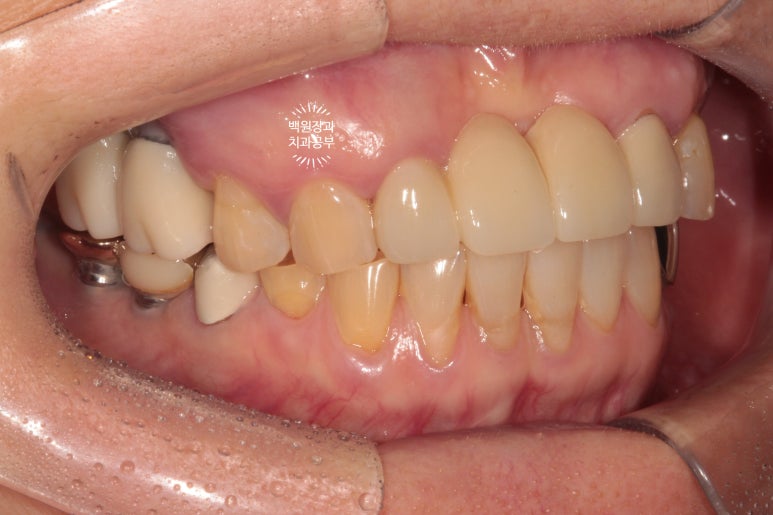

좌측은 깔끔하게 마무리된 지르코니아 브릿지를 보실 수 있네요 :)

씹는면에서 보면 그 깔끔함이 더 두드러집니다.

길어지는 임플란트 치료기간동안 앞니 지르코니아 브릿지 완성!

요기는 임플란트보다 다소 더 심미적인 브릿지를 원하셔서 앞니처럼 지르코니아 브릿지로 제작하기로 했습니다.

저희 치과는 지르코니아 크라운/브릿지 맛집이랍니다.